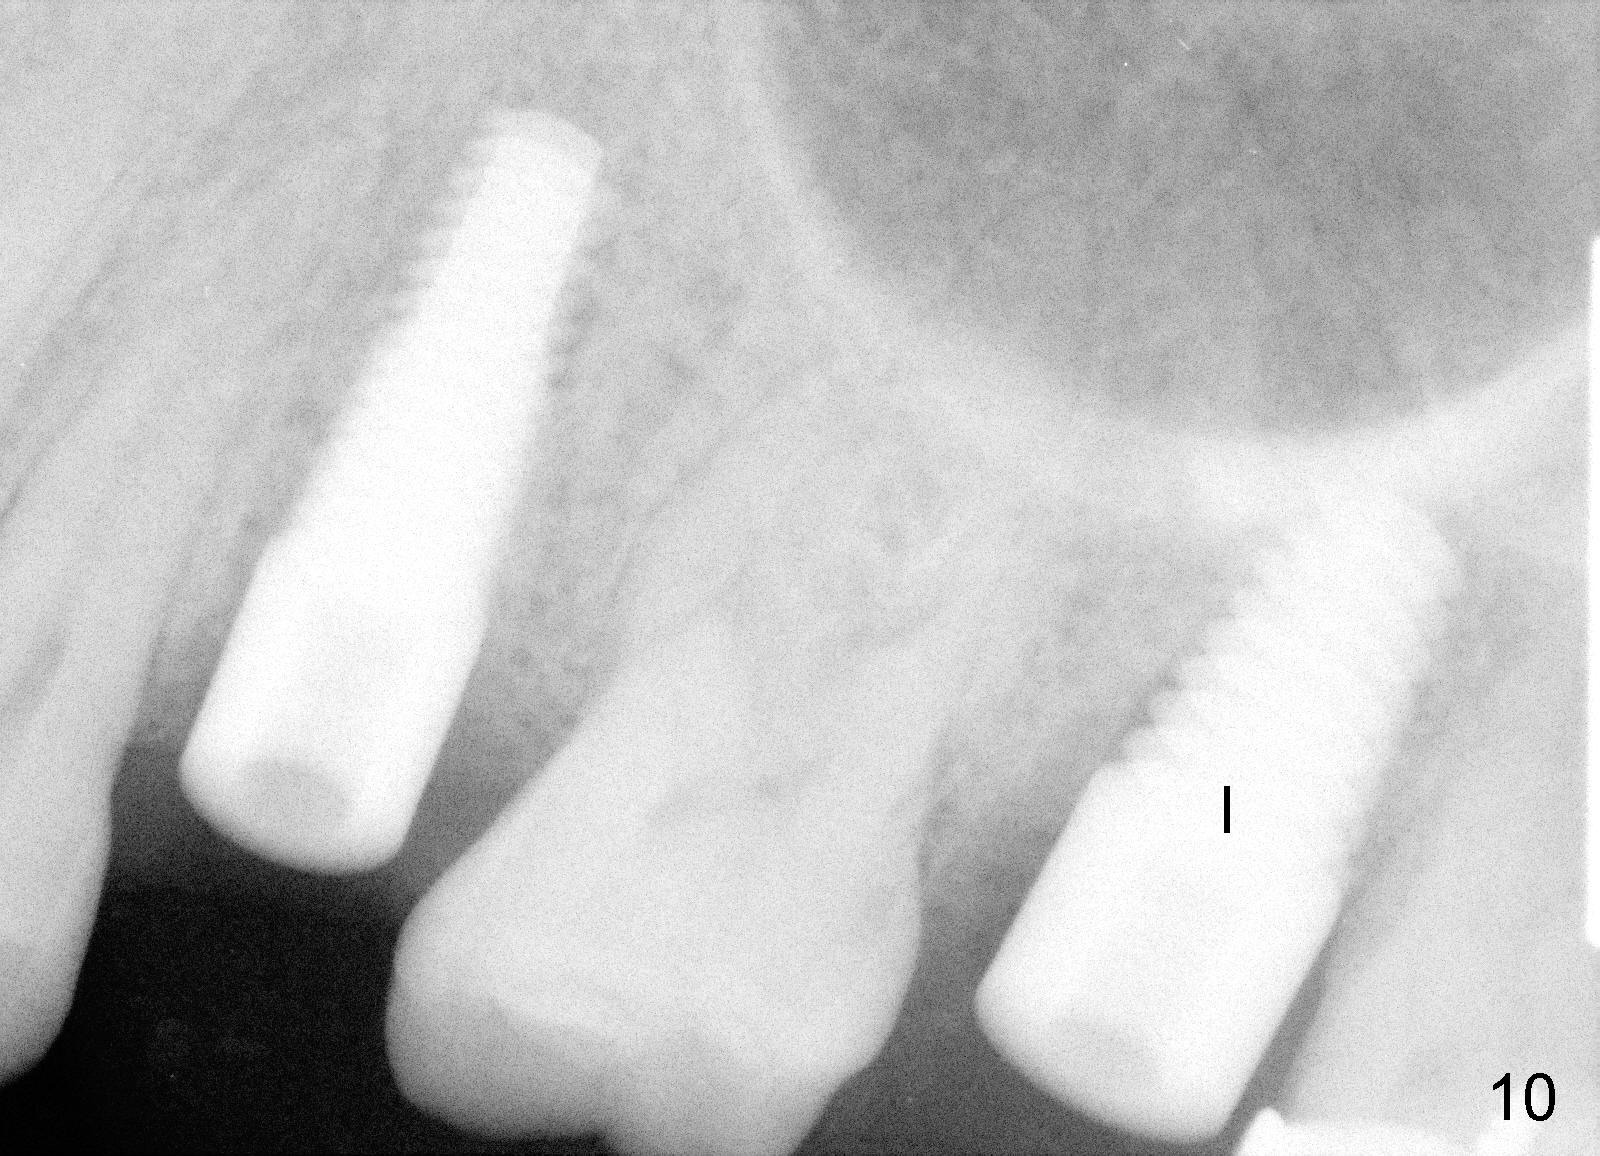

A 43-year-old lady has multiple nonsalvageable teeth. The first surgery involves two immediate implants in the upper left sextant (Fig.1: #13 and 15). The tooth #15 has 3 residual roots (MB, DB, P). There is no septum left between the first two roots when the tooth is extracted. A septum exists between the palatal (P) and buccal (B) sockets (Fig.2). Bone expansion technique is utilized to create an osteotomy in the septum. However, the smallest rounded tapered osteotome cannot be driven into the narrow septum; it slides (Fig.5). To get an initial engagement, a slot is created by high-speed surgical handpiece and fissure bur on the top of the septum. A series of blade-like osteotomes are inserted into the septum for sectioning (Fig.2 >). The smallest rounded osteotome is now easy to be inserted into the middle of the septum (Fig.3 circle, Fig.6 O). The septum is expanded by larger osteotomes (Fig.4 white circle; Fig.7 O) and tap (Fig.9 T). The septum continues being expanded when a 6x14 mm implant is placed (Fig.8,10 I). The insertion torque is more than 60 Ncm. No bone graft is placed. The palatal gap is closed by a palatal flap.